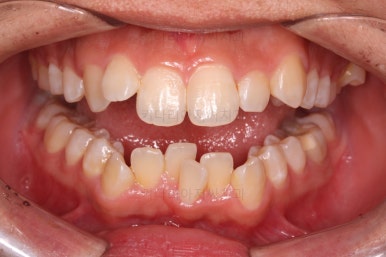

종료 시의 사진들을 전후 비교해 보겠습니다.

입매가 좋아졌고 입을 다무는 편안함도 좋아졌으며 치열이 가지런해졌으며 웃을 때 보이는 치열의 느낌도 좋고 교합도 잘 마무리 되었네요.

지켜봐도 되는 충치는 지켜보기로 여지를 남기고 필요한 충치치료도 마무리를 했습니다.

이상 부산청소년치아교정 키다리아저씨치과에서 시행한 덧니, 돌출입 개선 사례였습니다.